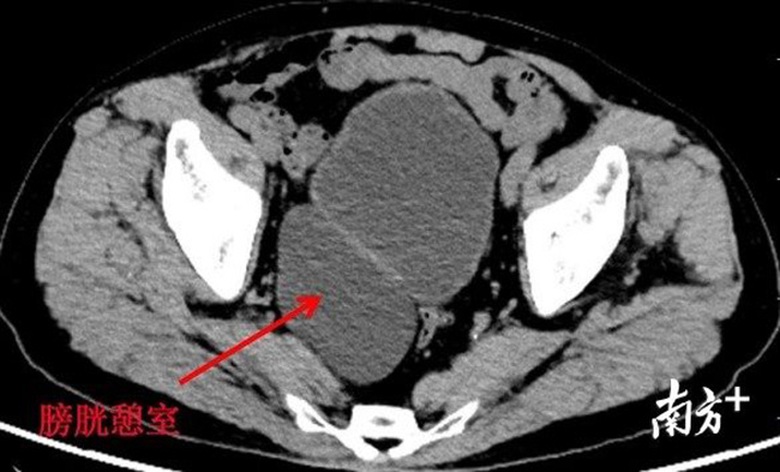

Bác sĩ Đới cho biết bệnh nhân có một phần nhô ra giống như vòng bít có đường kính gần 10 cm sau bàng quang. Nguyên nhân của tình trạng này được cho là do tiểu rắc làm tăng áp lực lên bàng quang. Thêm vào đó, tăng sản tuyến tiền liệt cũng là nguyên nhân chính gây ra tình trạng trên. Nếu không được chẩn đoán và điều trị kịp thời, bàng quang thứ 2 này sẽ gây ra nhiều biến chứng như sỏi, khối u và làm cho chức năng chính của bàng quang bị suy yếu.

Bàng quang thứ 2 được xác định là một sự thay đổi bệnh lý của bàng quang. Nó là một túi thừa phình ra khỏi niêm mạc bàng quang, thông qua lớp cơ của thành bàng quang chính. Cái túi thừa này giống như da nhưng không co giãn. Nó không thể co bóp, dẫn tới nước tiểu bên trong không thoát ra được, có khả năng đi kèm với trào ngược bàng quang niệu quản.